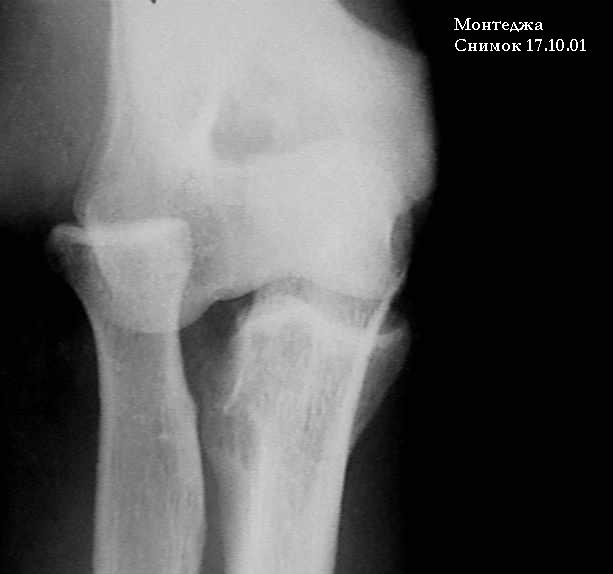

У больного травма в октябре 2001. Перелом Монтеджа разгибательный.Проведена операция металлостеосинтез пластиной, винтами локтевой кости. Вывих головки лучевой кости не диагностирован. В конце февраля 2002 г снята гипсовая повязка. Имеется ограничение сгибания до 115 градусов. Больной обратился в наше лечебное учреждение 07.02.02. Мы предложили ему оперативное лечение. Планируем провести резекцию головки лучевой кости. Есть мнение попытаться вправить головку лучевой кости, провести пластику кольцевидной связки, фиксисировать головку лучевой кости трансартикулярно спицей. Но боюсь, что в момент остеосинтеза была укорочена локтевая кость, поэтому необходимо будет провести резкцию в области диафиза лучевой кости, а затем провести остеосинтез лучевой кости. Рентгенограммы: